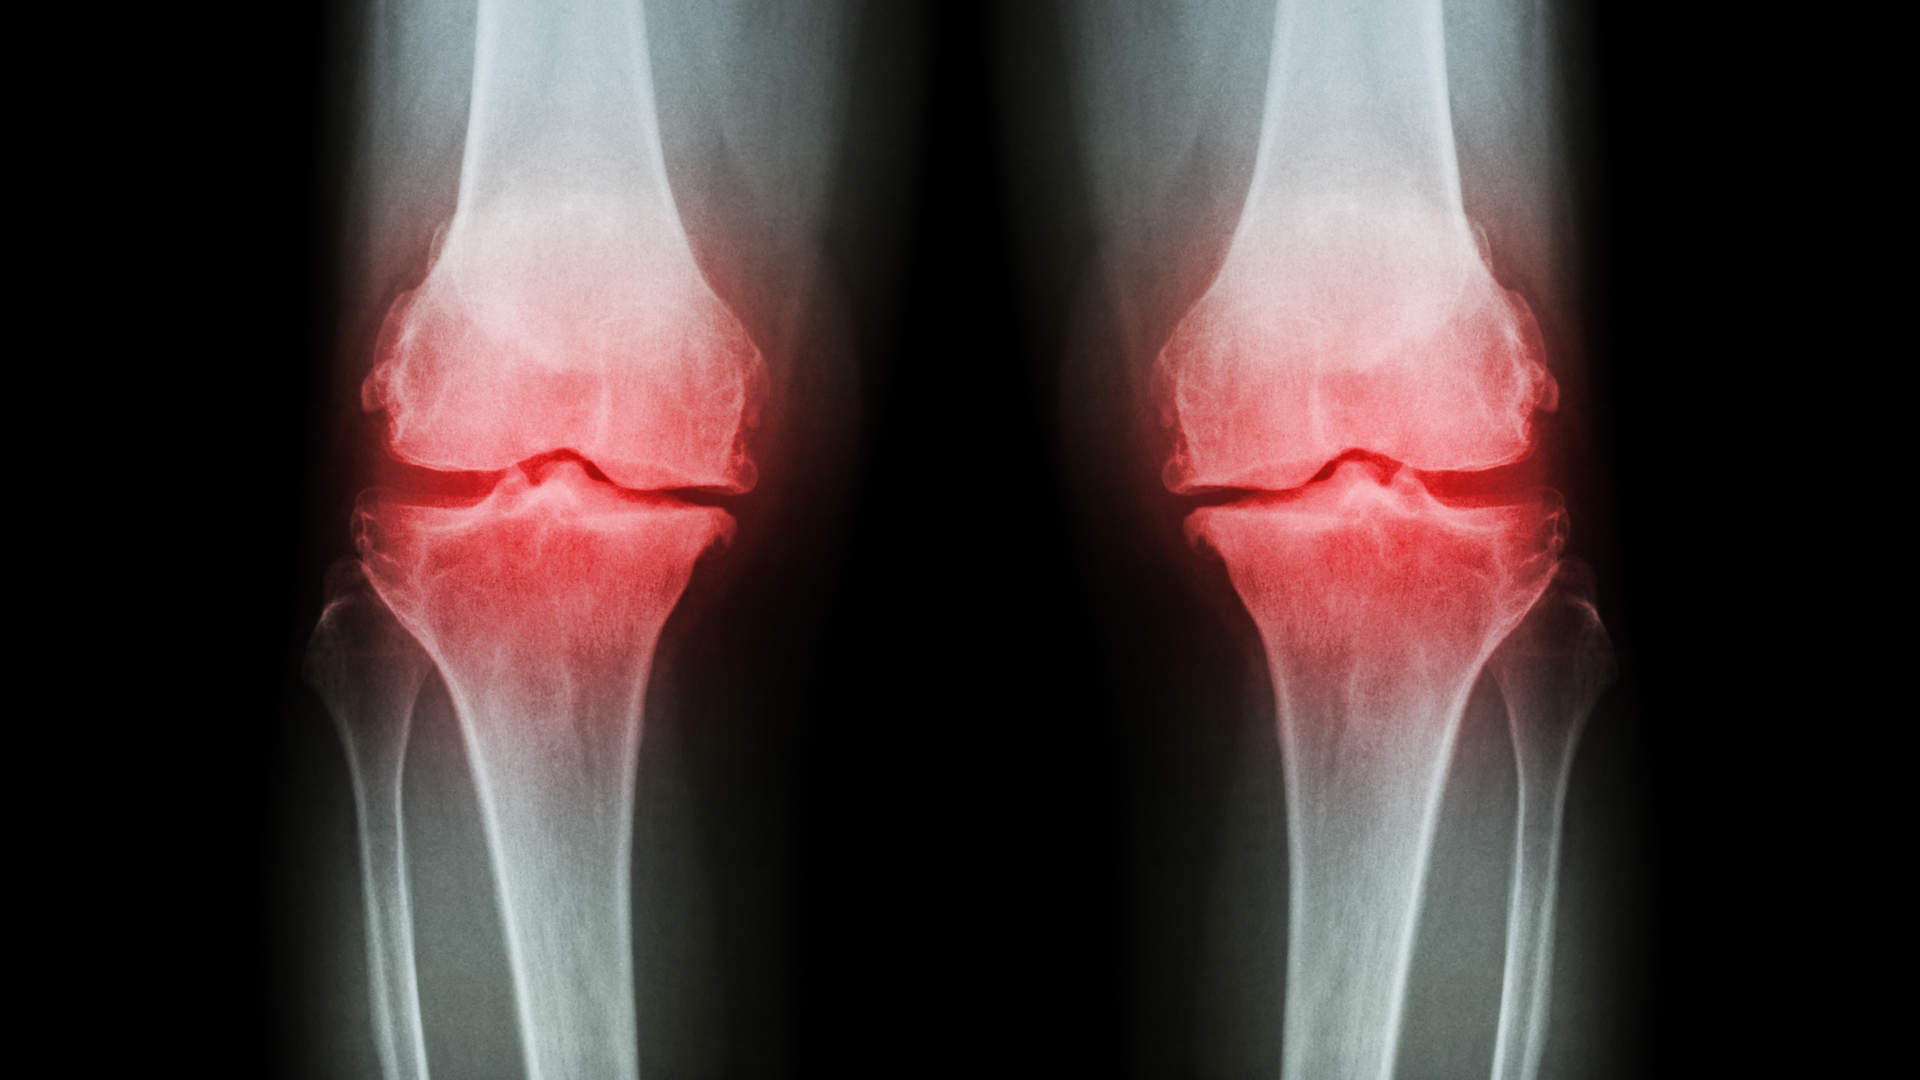

Osteoarthritis is widespread, affecting more than 50 million people in the U.S. with no known treatment that can prevent its progression. The condition can require expensive joint replacement surgeries, lead to disabilities and significantly affect quality of life. Its burden on the healthcare system continues to rise, said Baker, with an aging population and higher rates of obesity.

The authors found that if a patient had asthma or eczema, there was a 58% increased risk of developing osteoarthritis over about 10 years. If they had both asthma and eczema, the risk increased to 115%.